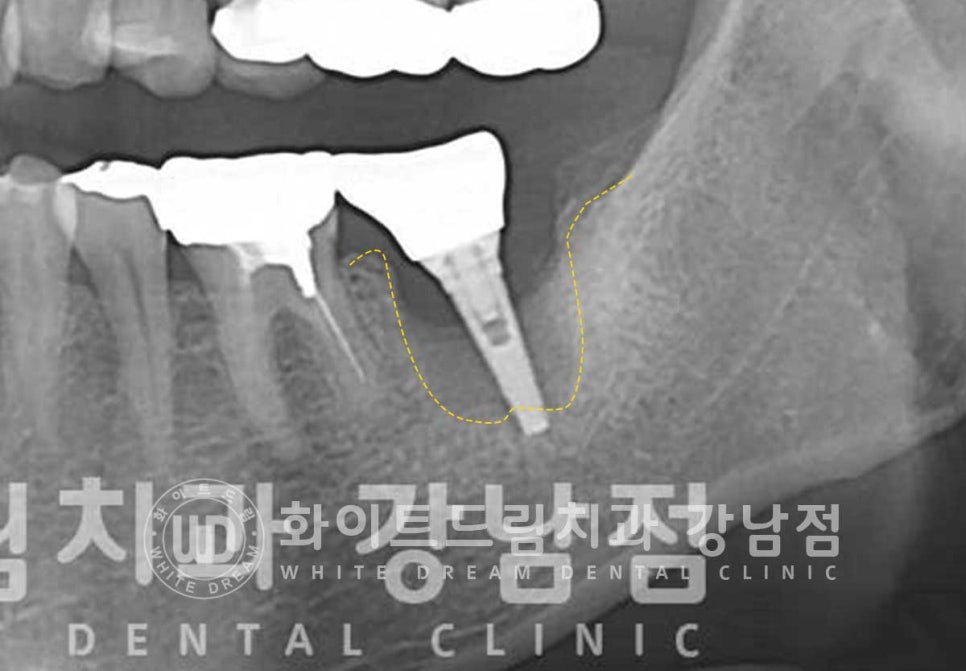

임플란트의 상태를 보니 주위 염증이 심하게 발생하고

잇몸뼈도 많이 녹아내린 상태이며 임플란트 끝부분이 잇몸뼈에 겨우 붙어 있는 상태였습니다.

보통 주위염이 발생하면 1/3 정도까지는 잇몸치료를 통해 조금 더 사용할 수 있게 하지만

이렇게 2/3 이상의 잇몸뼈가 녹은 경우는 대부분 임플란트 제거 후 재식립을 고려하게 됩니다.